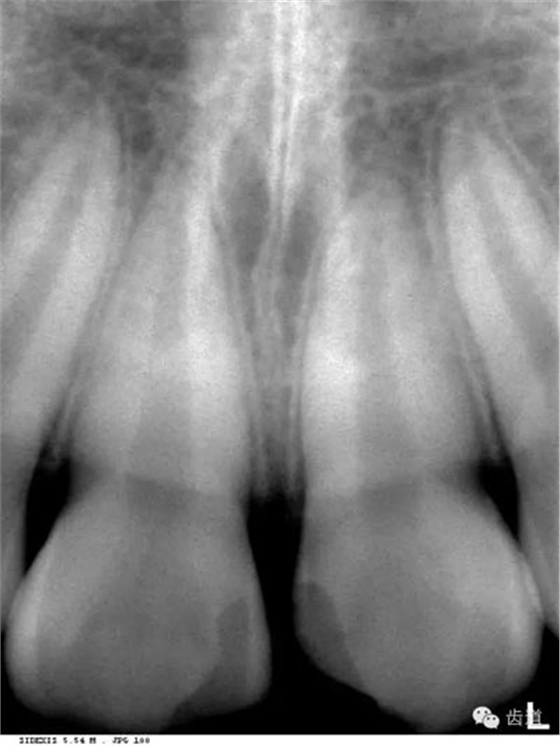

在兩個(gè)中切牙牙根之間或稍上方,多呈橢圓形密度低的影像,切牙孔影像可重疊在一側(cè)中切牙牙根尖處,易誤認(rèn)為根尖周病變,可視牙周膜和骨硬板是否完整加以鑒別

位于兩側(cè)中切牙牙根之間,由牙槽突向上,呈直線狀密度低的影像。其兩側(cè)為密度高的影像,為兩側(cè)上頜骨腭突的致密骨層。

鼻腔位于上切牙根尖的上方,顯示為對(duì)稱性半圓形密度低的影像,其中間被一密度高的骨隔分開為鼻中隔